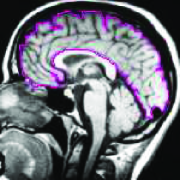

An ideal method improves both optimizibility and fidelity without sacrificing either property (green contour in Figure 5).